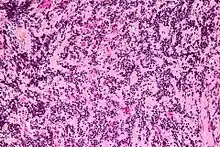

| Micrograph of a pineocytoma. HPS stain. | |